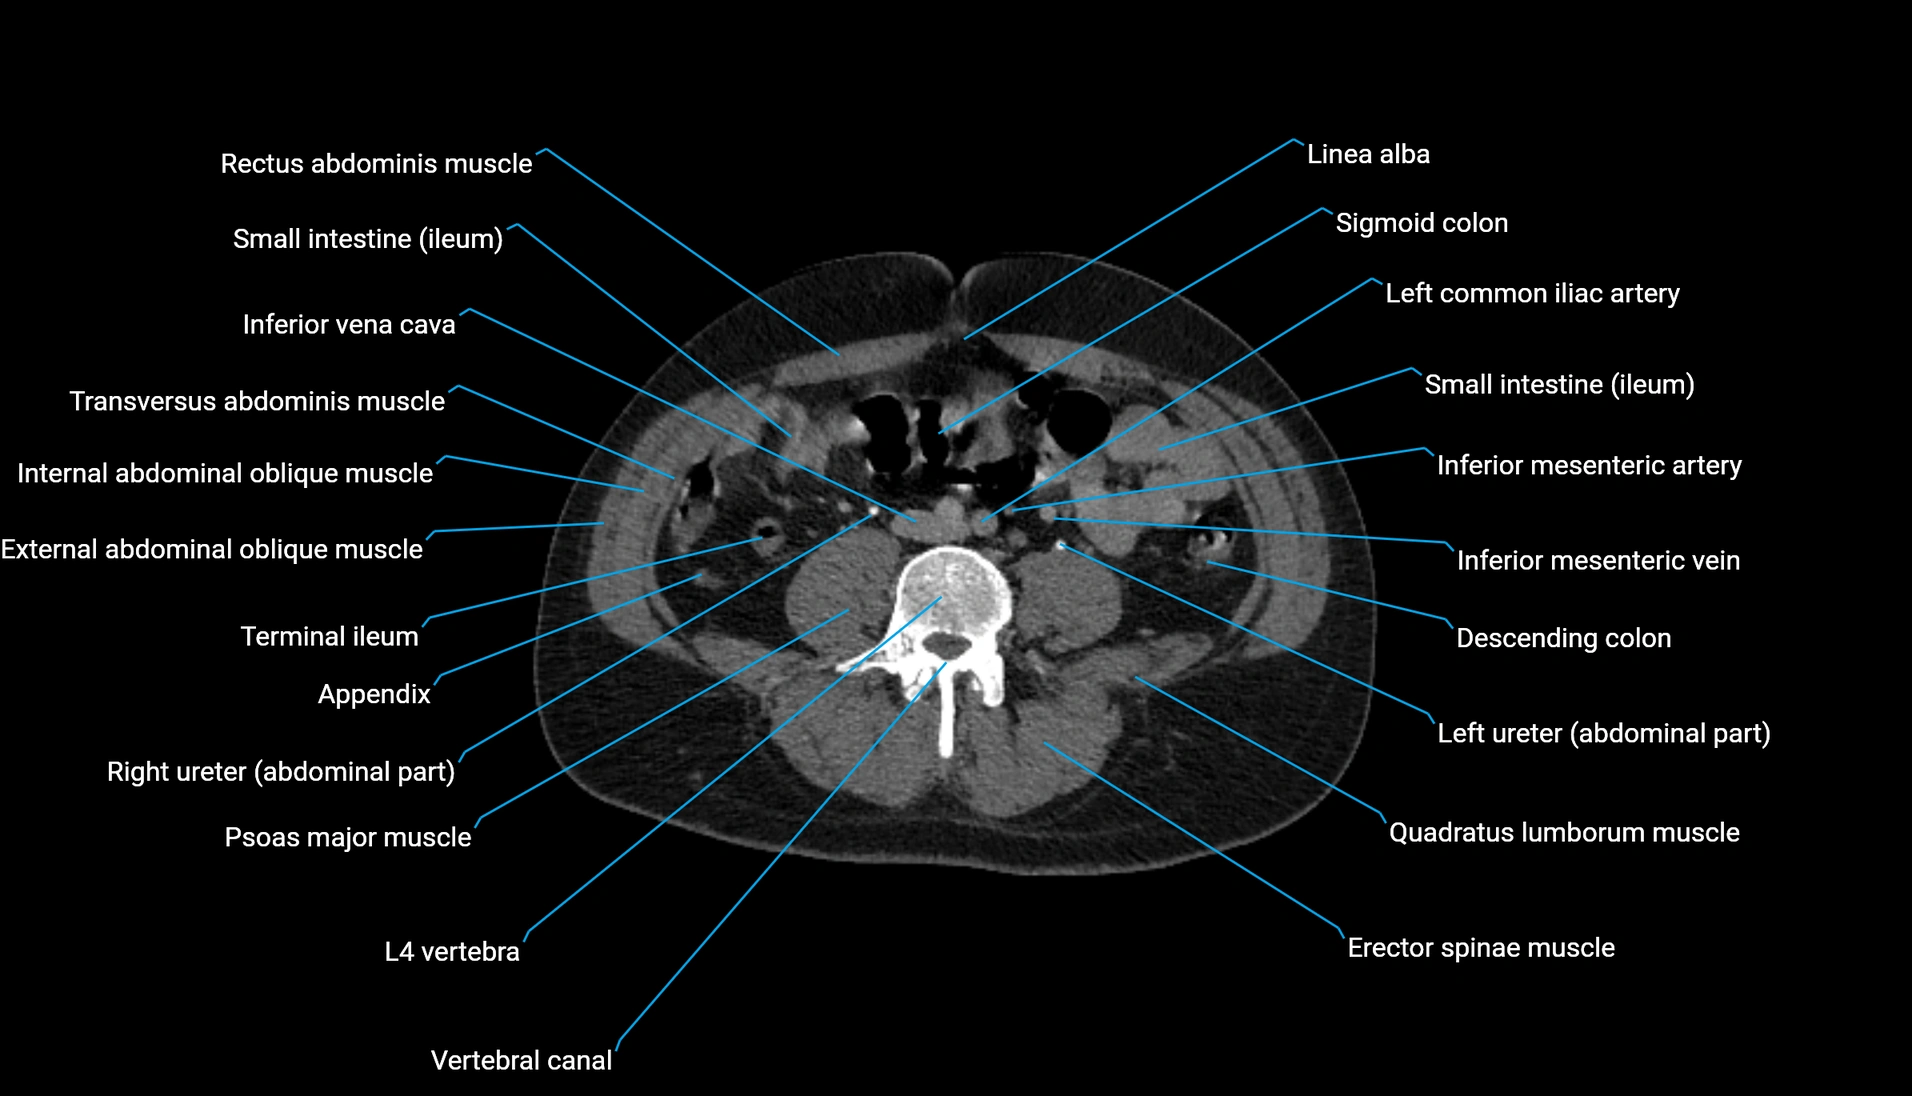

CT image